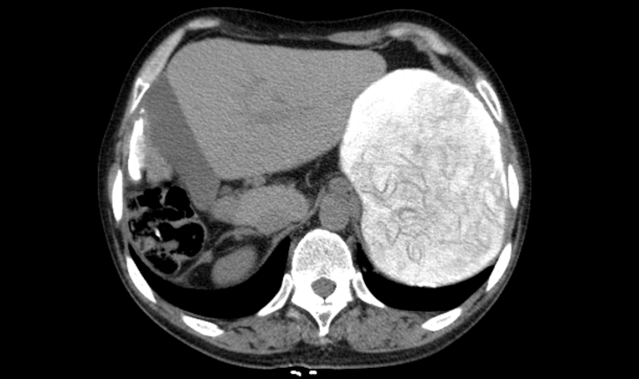

蒋宗华主任凭借多年对肝包虫病发展过程中的研究分析了解,结合患者病情及相关检查后,考虑该患者虽然既往做过包虫手术造成肝右叶部分缺如,现再次复发巨大肝包虫,位置且在肝胃间系间呈现巨大椭圆形高密度,边界清晰,大小约148mm*100mm,手术难度大,风险高,但仍有把握完成其“肝包虫外囊摘除术”,本着医院“患者需求至上”的核心价值观,西藏阜康医院普外科决定收治该患者。

红色闪动部分为患者肝包虫区域